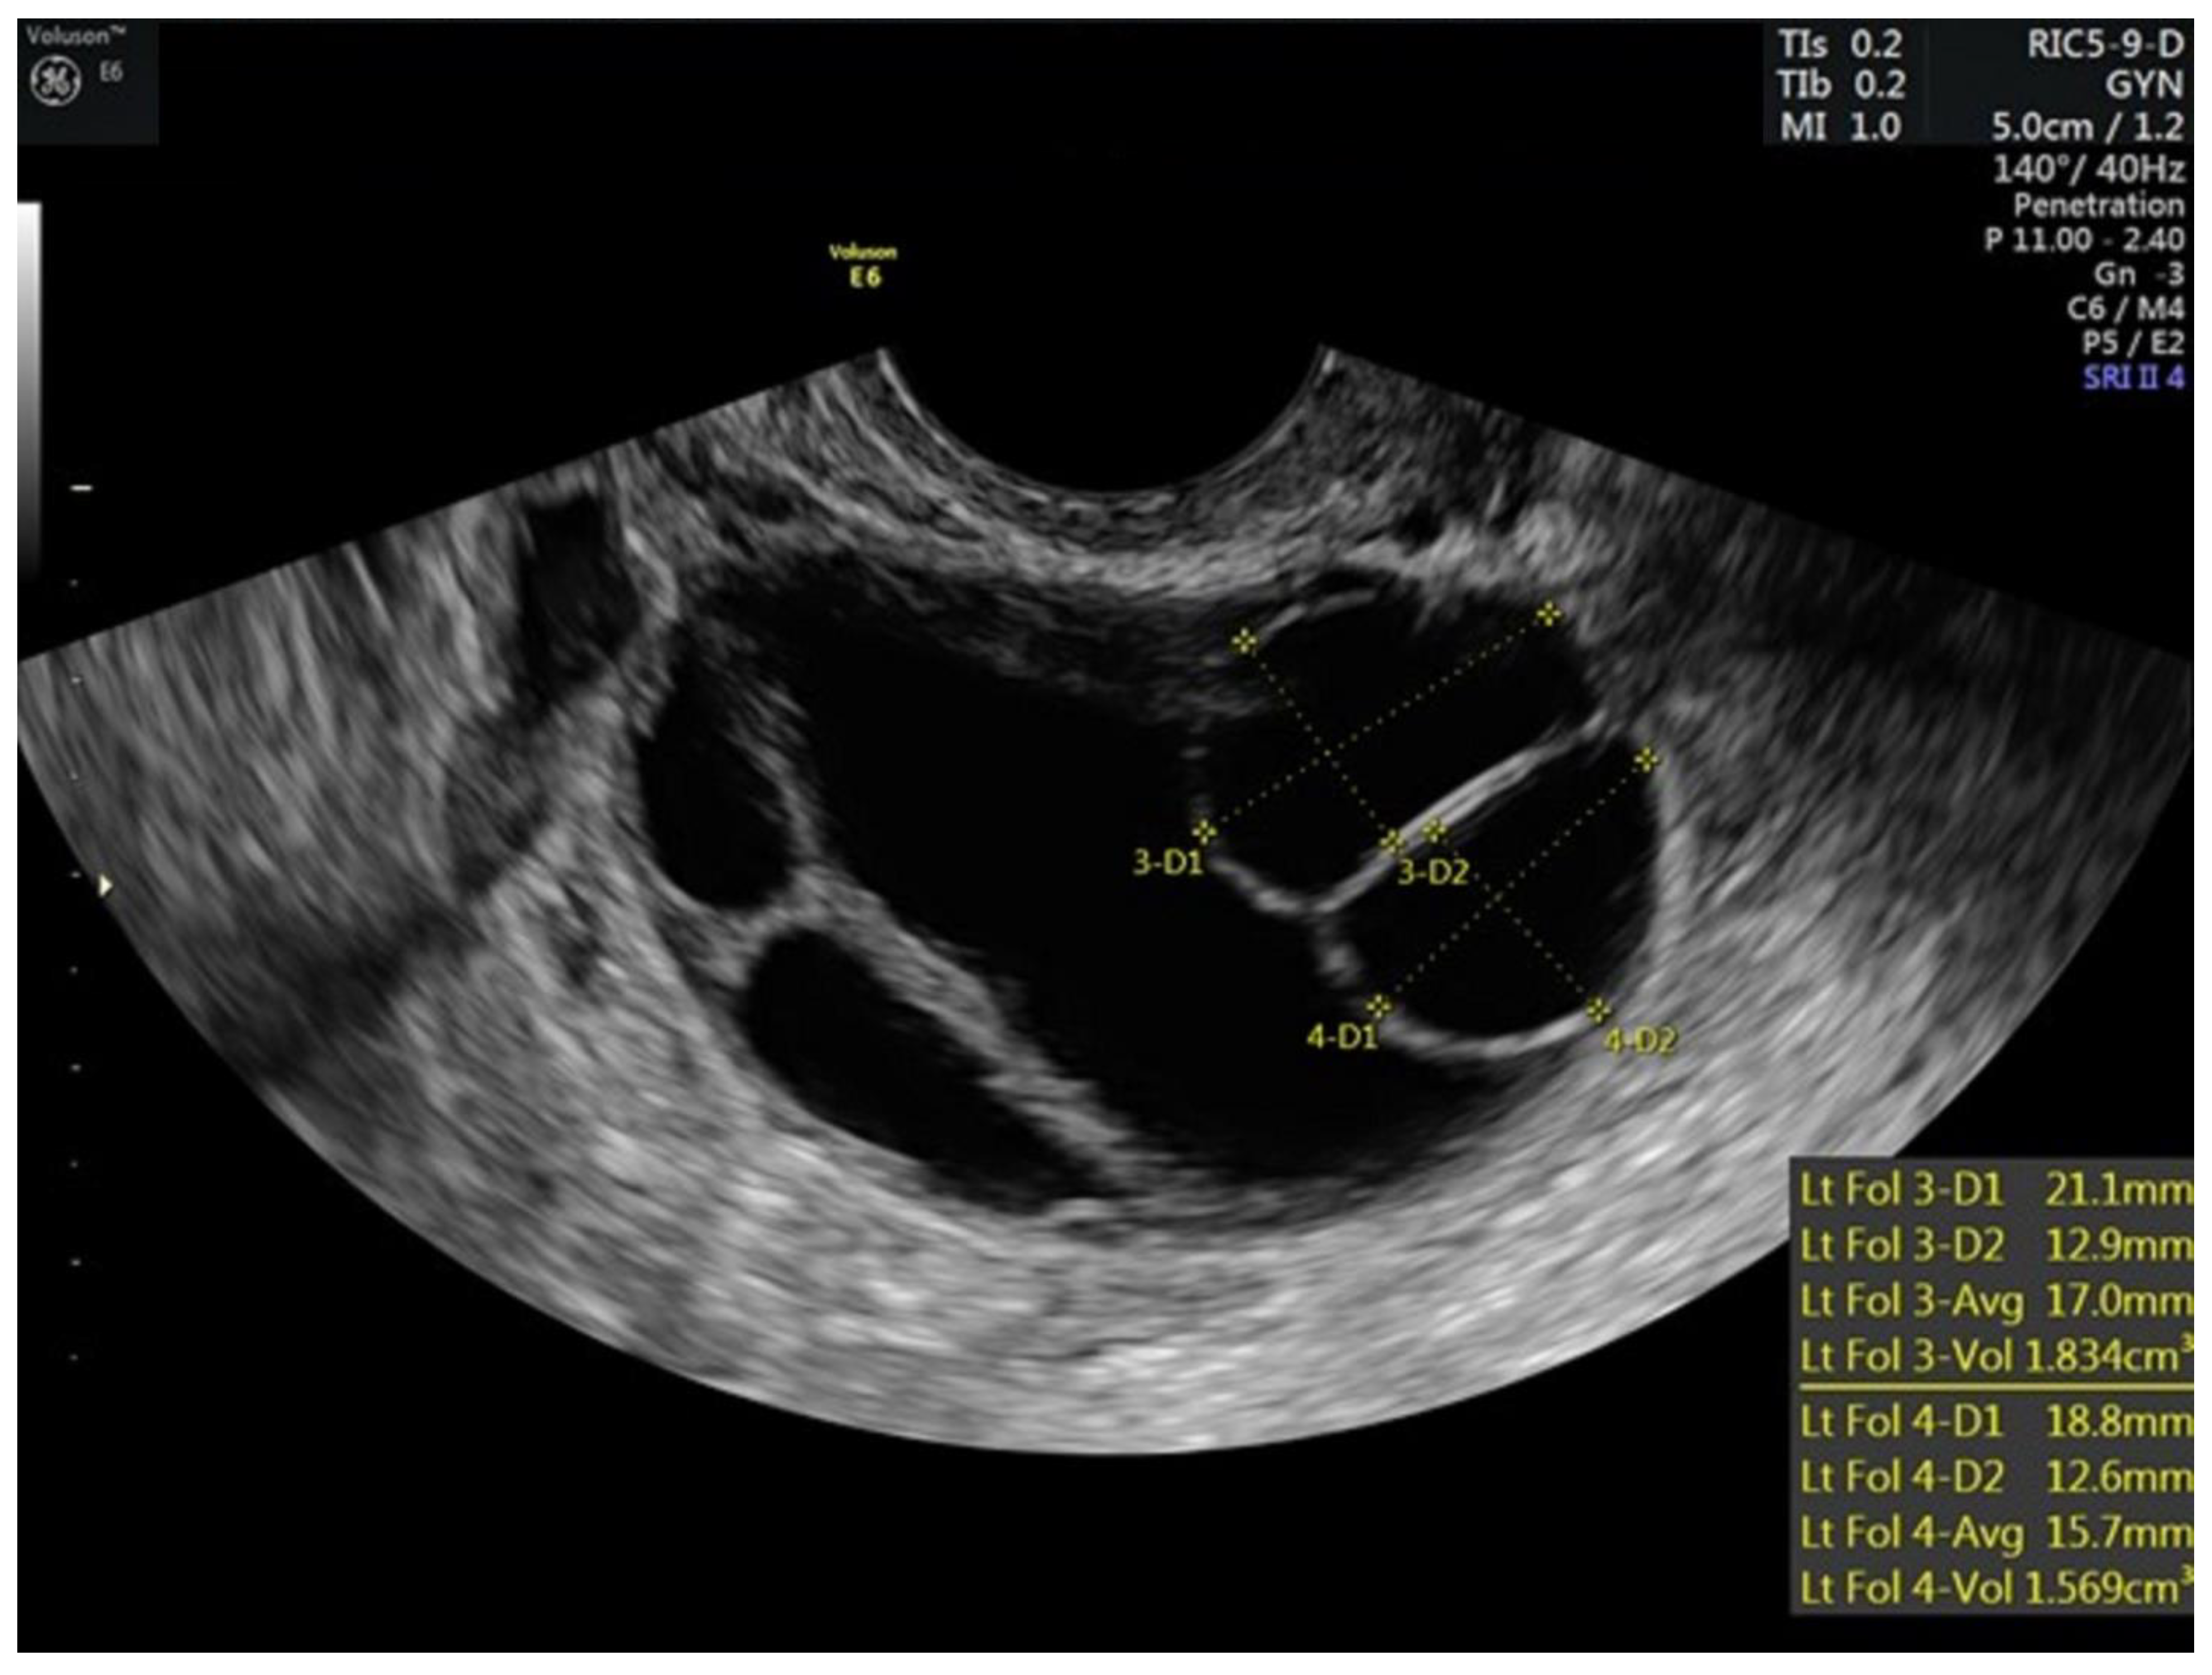

| 10 | 5 | 40 | 100 | 75 | 250 | 172 | 0.6 | 19,17,17,13,12,12,9,6 | 18,17,16,16,13,4 | 5.3 | ||